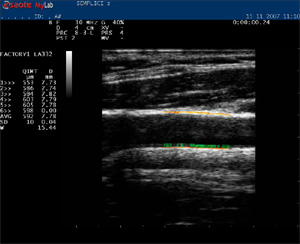

Кардиологи из 13 европейских центров принимают участие в этом проекте. На сегодняшний день проанализированы результаты исследований сонных артерий технологией eTRACKING компании Hitachi Aloka Medical с использованием ультразвукого датчика для сосудистых исследований более чем у 2 000 пациентов.

Подобные ультразвуковые технологии существую у все ведущих производителей ультразвуковых аппаратов, так например в компании Esaote - RFQIMT & RFQAS, GE – измерение комплекса IMT/AS.

Фото 1; 2 Ультразвуковые технологии компаний Hitachi Aloka Medical и Esaote измерения комплекса интима-медиа и ригидности аорты